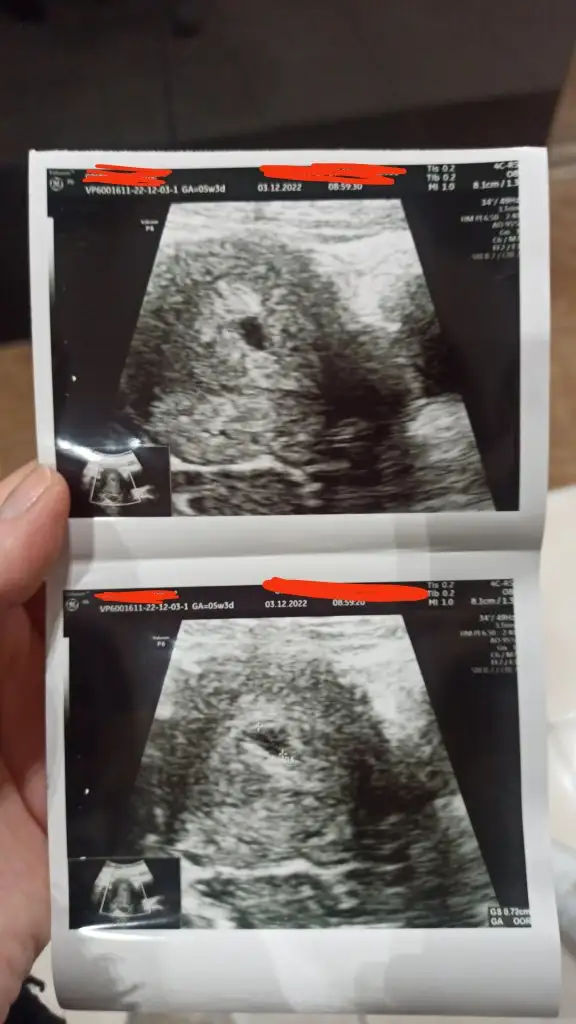

Hayırlı olsunKızlar dün kontrolüm vardı vee keseyi gördük çok şükür3 hafta sonra kontrole çağırdı nasıl geçecek 3 hafta bilmiyorummm Eki Görüntüle 3171372